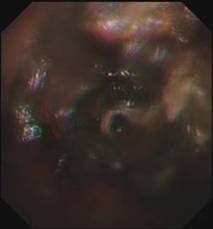

时间紧迫,每一秒都关乎生命,患者立即被送到内镜室,支气管镜检查的结果令人触目惊心:患者的总气管被痰痂、血痂、痰栓等物几乎完全堵死,仅残留一丝细小的通气通道,那是生命最后的脆弱纽带!

在紧张且充满紧迫感的抢救氛围中,呼吸介入团队成员默契配合,在支气管镜下使用异物钳夹取、超低温冷冻等方法清除异物。

随着每一次精准夹取和冷冻操作,顽固的异物被一点点从狭窄的气道内剥离出来,堆积在一旁的痰痂、血痂和痰栓逐渐增多,堆积起来的长度居然达到了惊人的18厘米。

当最后一块异物被取出,患者的气管终于露出了原来的“庐山真面目”: